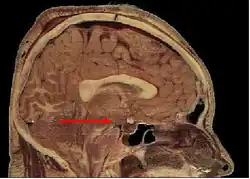

Синдро́м Не́льсона — заболевание, характеризующееся хронической надпочечниковой недостаточностью, гиперпигментацией кожного покрова, слизистых оболочек и наличием опухоли гипофиза[1]. Данный синдром можно рассматривать как своеобразное осложнение после лечения болезни Кушинга методом двусторонней адреналэктомии, либо длительной терапии хлодитаном[2].

При синдроме Нельсона формируются макроаденомы, наблюдается выраженный клеточный и ядерный полиморфизм, много митозов, обусловливающих быстрый и агрессивный рост. Развитие синдрома Нельсона наблюдается даже на фоне заместительной терапии кортикостероидами, в случаях когда получаемые дозы препаратов недостаточны для подавления кортикотрофов[2].

Лабораторная и инструментальная диагностика проводится по результатам исследования уровня АКТГ и подтверждения наличия микро или макроаденомы гипофиза, характеристики ее роста, оценки динамики роста аденомы в сравнении с периодом после двусторонней адреналэктомии до развития заболевания. Для кортикотропиномы в условиях удаленных надпочечников характерно повышение уровня АКГТ более 200 пг/мл, а также отсутствие циркадианного ритма секреции. Величина АКТГ отражает активность аденомы и соответствует выраженности гиперпигментации. При быстро растущих аденомах с инфильтративным ростом и резко выраженной гиперпигментацией уровень АКГТ способен достигать 3000 пг/мл и более.[8]